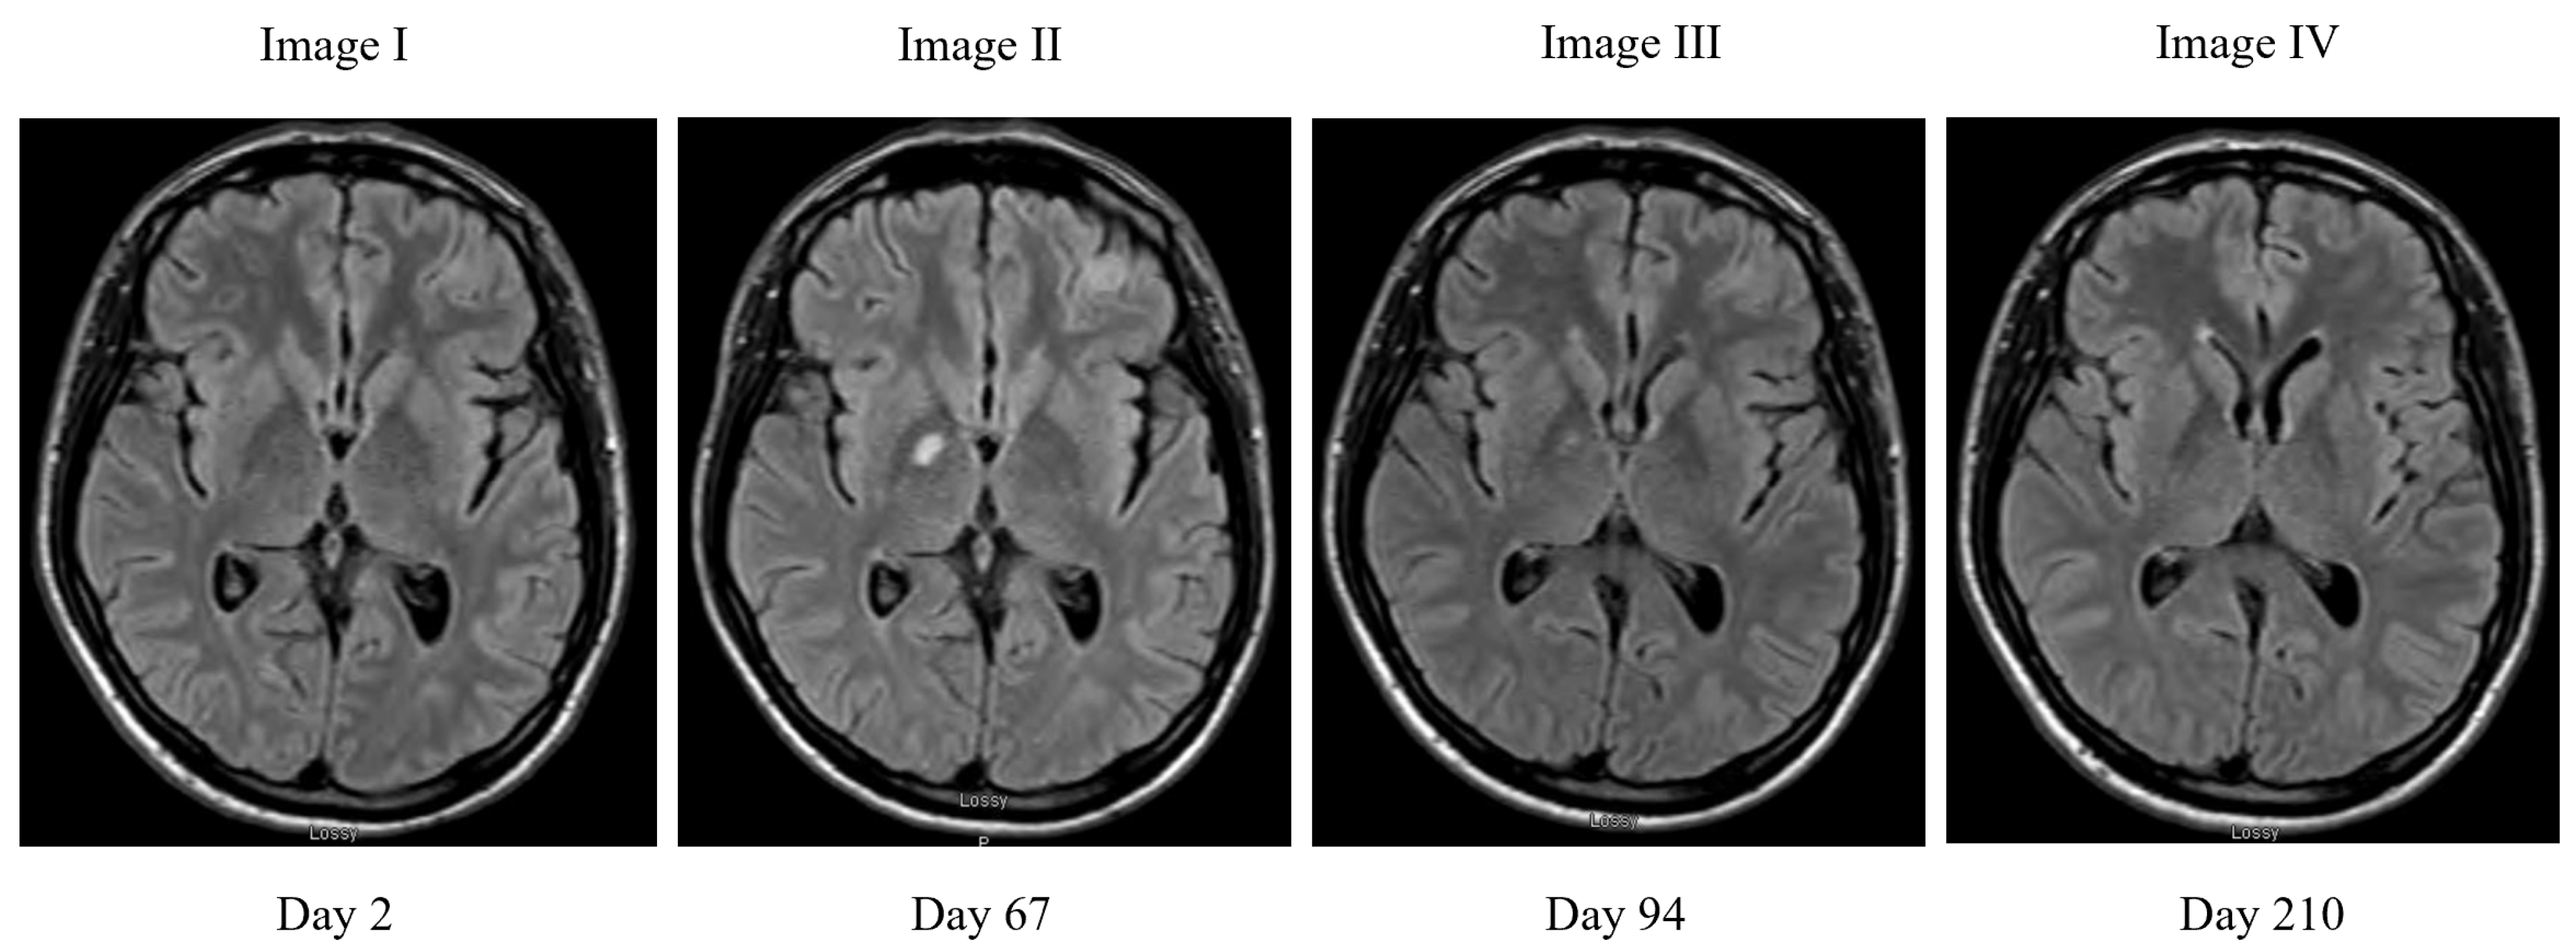

2. Case